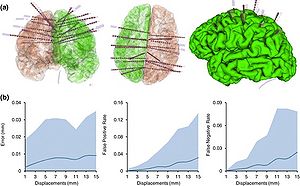

Publication: Int J Comput Assist Radiol Surg. 2016 Mar;11(3):473-81. PMID: 26183148 Authors: De Momi E, Ferrigno G, Bosoni G, Bassanini P, Blasi P, Casaceli G, Fuschillo D, Castana L, Cossu M, Lo Russo G, Cardinale F. Institution: Department of Electronics, Information and Bioengineering (DEIB), Politecnico di Milano, Milan, Italy. Background/Purpose: Image guidance is widely used in neurosurgery. Tracking systems (neuronavigators) allow registering the preoperative image space to the surgical space. The localization accuracy is influenced by technical and clinical factors, such as brain shift. This paper aims at providing quantitative measure of the time-varying brain shift during open epilepsy surgery, and at measuring the pattern of brain deformation with respect to three potentially meaningful parameters: craniotomy area, craniotomy orientation and gravity vector direction in the images reference frame. Methods: We integrated an image-guided surgery system with 3D Slicer, an open-source package freely available in the Internet. We identified the preoperative position of several cortical features in the image space of 12 patients, inspecting both the multiplanar and the 3D reconstructions. We subsequently repeatedly tracked their position in the surgical space. Therefore, we measured the cortical shift, following its time-related changes and estimating its correlation with gravity and craniotomy normal directions. Results: The mean of the median brain shift amount is 9.64 mm ([Formula: see text] mm). The brain shift amount resulted not correlated with respect to the gravity direction, the craniotomy normal, the angle between the gravity and the craniotomy normal and the craniotomy area. Conclusions:Our method, which relies on cortex surface 3D measurements, gave results, which are consistent with literature. Our measurements are useful for the neurosurgeon, since they provide a continuous monitoring of the intra-operative sinking or bulking of the brain, giving an estimate of the preoperative images validity versus time. |